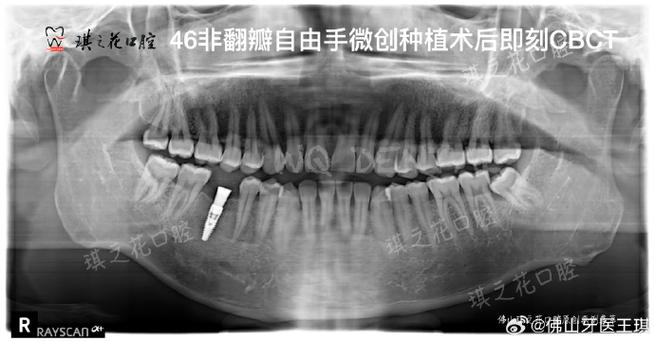

- CBCT(锥形束CT)精准影像评估: 精确测量骨量、骨密度、重要解剖结构(神经管、上颌窦)的位置。

- 3D种植导板: 这是实现微创的关键工具,术前利用CBCT数据结合口内扫描或模型扫描,在电脑上进行虚拟种植设计,制作个性化的手术导板,术中导板能精确引导种植钻头的方向、角度和深度,确保种植体按预定方案精准植入,避免不必要的翻瓣和骨去除,实现“盲种”变“可视种”。